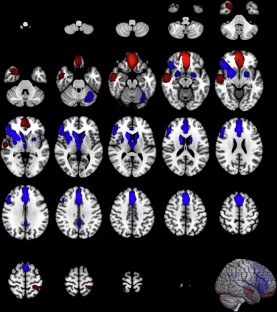

Brain functional alterations associated with overall cognitive impairments and specific cognitive domains defined by MATRICS Consensus Cognitive Battery (MCCB) and the similarities among them remain unclear in schizophrenia. Comprehensive literature review and meta-analyses of cognitive task fMRI studies were conducted to identify whole-brain differences between schizophrenia patients and healthy controls, and subgroup analyses were also conducted for each MCCB domain. Identified brain regions were mapped onto canonical brain networks. The similarity analyses between network dysfunction obtained for paired subgroup analyses with and without each MCCB domain, and between each MCCB domain and primary analysis, were calculated after controlling for sample size. Meta-regression analyses were conducted between brain alterations and demographic and clinical characteristics. The present meta-analysis encompassed 232 datasets with 5229 schizophrenia patients and 6132 healthy controls. In primary analysis, schizophrenia patients showed significant brain dysfunctions mainly within default mode and subcortical networks. Distinct brain dysfunctions for each MCCB domain were also identified. Sample size-weighted similarity analyses revealed that network alterations associated with working memory deficits, among the seven, showed the greatest convergence with brain changes identified in subgroup analysis without this domain and primary analysis (sample size-weighted Dice coefficients = 0.24 and 0.51). Significant correlations were identified between significant brain alterations and negative symptoms and years of education. Aberrant activations in default mode and subcortical networks in working memory domain showed higher similarity than those observed in the other six cognitive domains, indicating functional integration of working memory and functional specialization of remaining cognitive domains in schizophrenia.